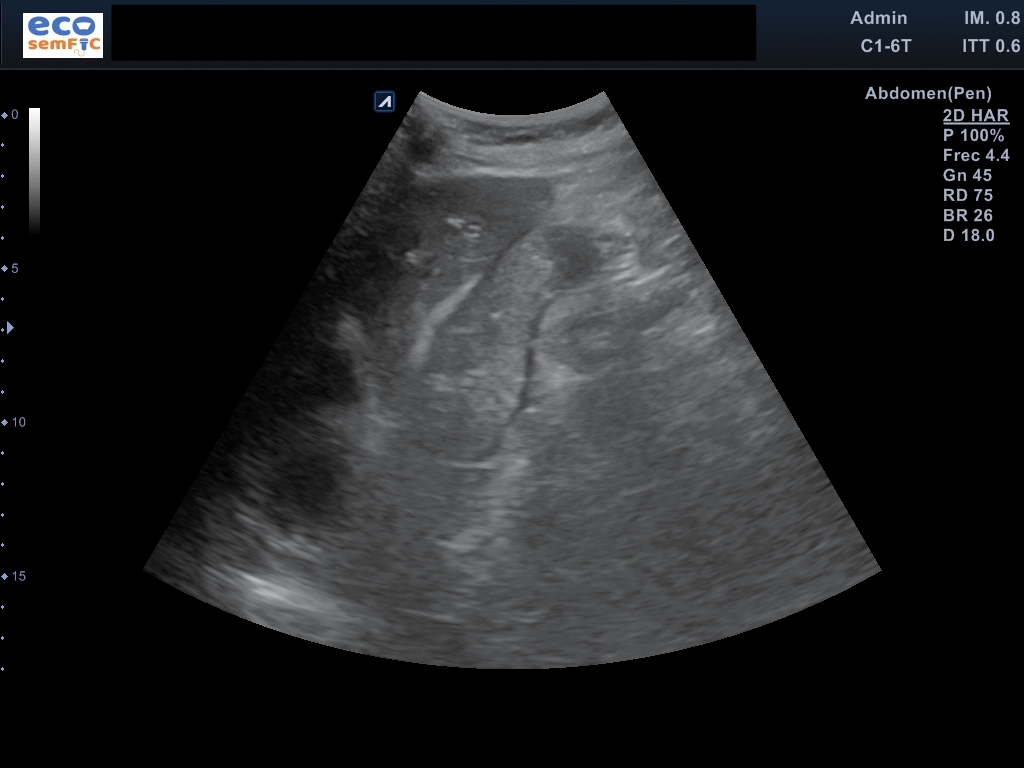

Limitada por poca colaboración, pero aceptable. En las áreas accesibles, hígado de superficie lisa y contorno regular, heterogéneo sin aparentes LOEs. Radicales intrahepáticos dependientes del conducto hepático derecho ectásicos. Colédoco proximal de 8,3 mm y distal de 14,3 mm a nivel de la cabeza del páncreas. Marco duodenal ocupado por contenido sólido aperistáltico en este momento. Páncreas visualizado en toda su extensión con Wirsung patente no dilatado, sin lesiones focales. Riñones de aspecto senil, conservan el grosor cortical y diferenciación parénquima-seno. Bazo homogéneo no aumentado ni lesiones parenquimatosas. Ausencia líquido libre o colecciones en áreas exploradas.